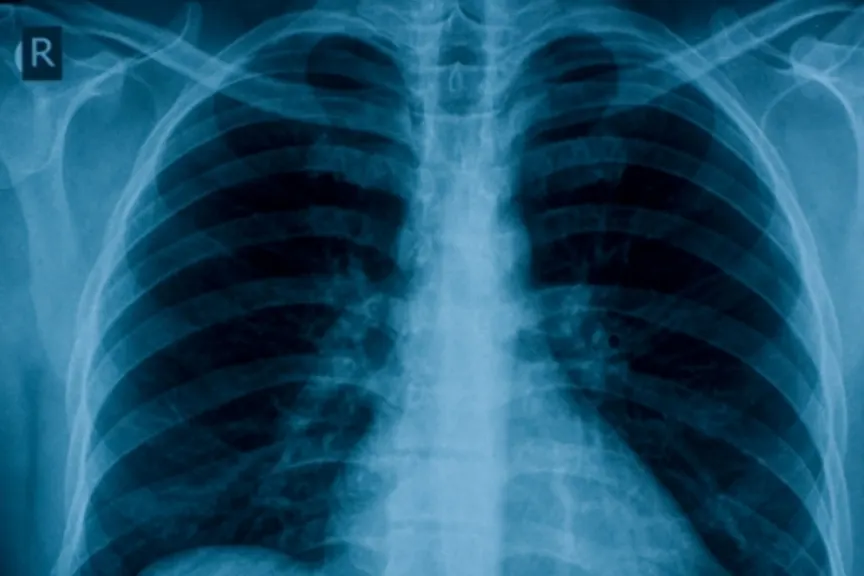

避免肺部感染的6种方法

的人慢性阻塞性肺病和其他相关的呼吸系统疾病,这些提示可以帮助防止突发。